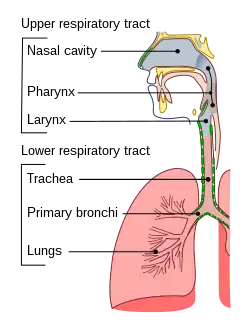

The common cold or the cold is a viral infectious disease of the upper respiratory tract that primarily affects the respiratory mucosa of the nose, throat, sinuses, and larynx.[6][8] Signs and symptoms may appear fewer than two days after exposure to the virus.[6] These may include coughing, sore throat, runny nose, sneezing, headache, and fever.[3][4] People usually recover in seven to ten days,[3] but some symptoms may last up to three weeks.[7] Occasionally, those with other health problems may develop pneumonia.[3]

The distinction between viral upper respiratory tract infections is loosely based on the location of symptoms, with the common cold affecting primarily the nose (rhinitis), throat (pharyngitis), and lungs (bronchitis).[8] There can be significant overlap, and more than one area can be affected.[8] Self-diagnosis is frequent.[4] Isolation of the viral agent involved is rarely performed,[48] and it is generally not possible to identify the virus type through symptoms.[4]